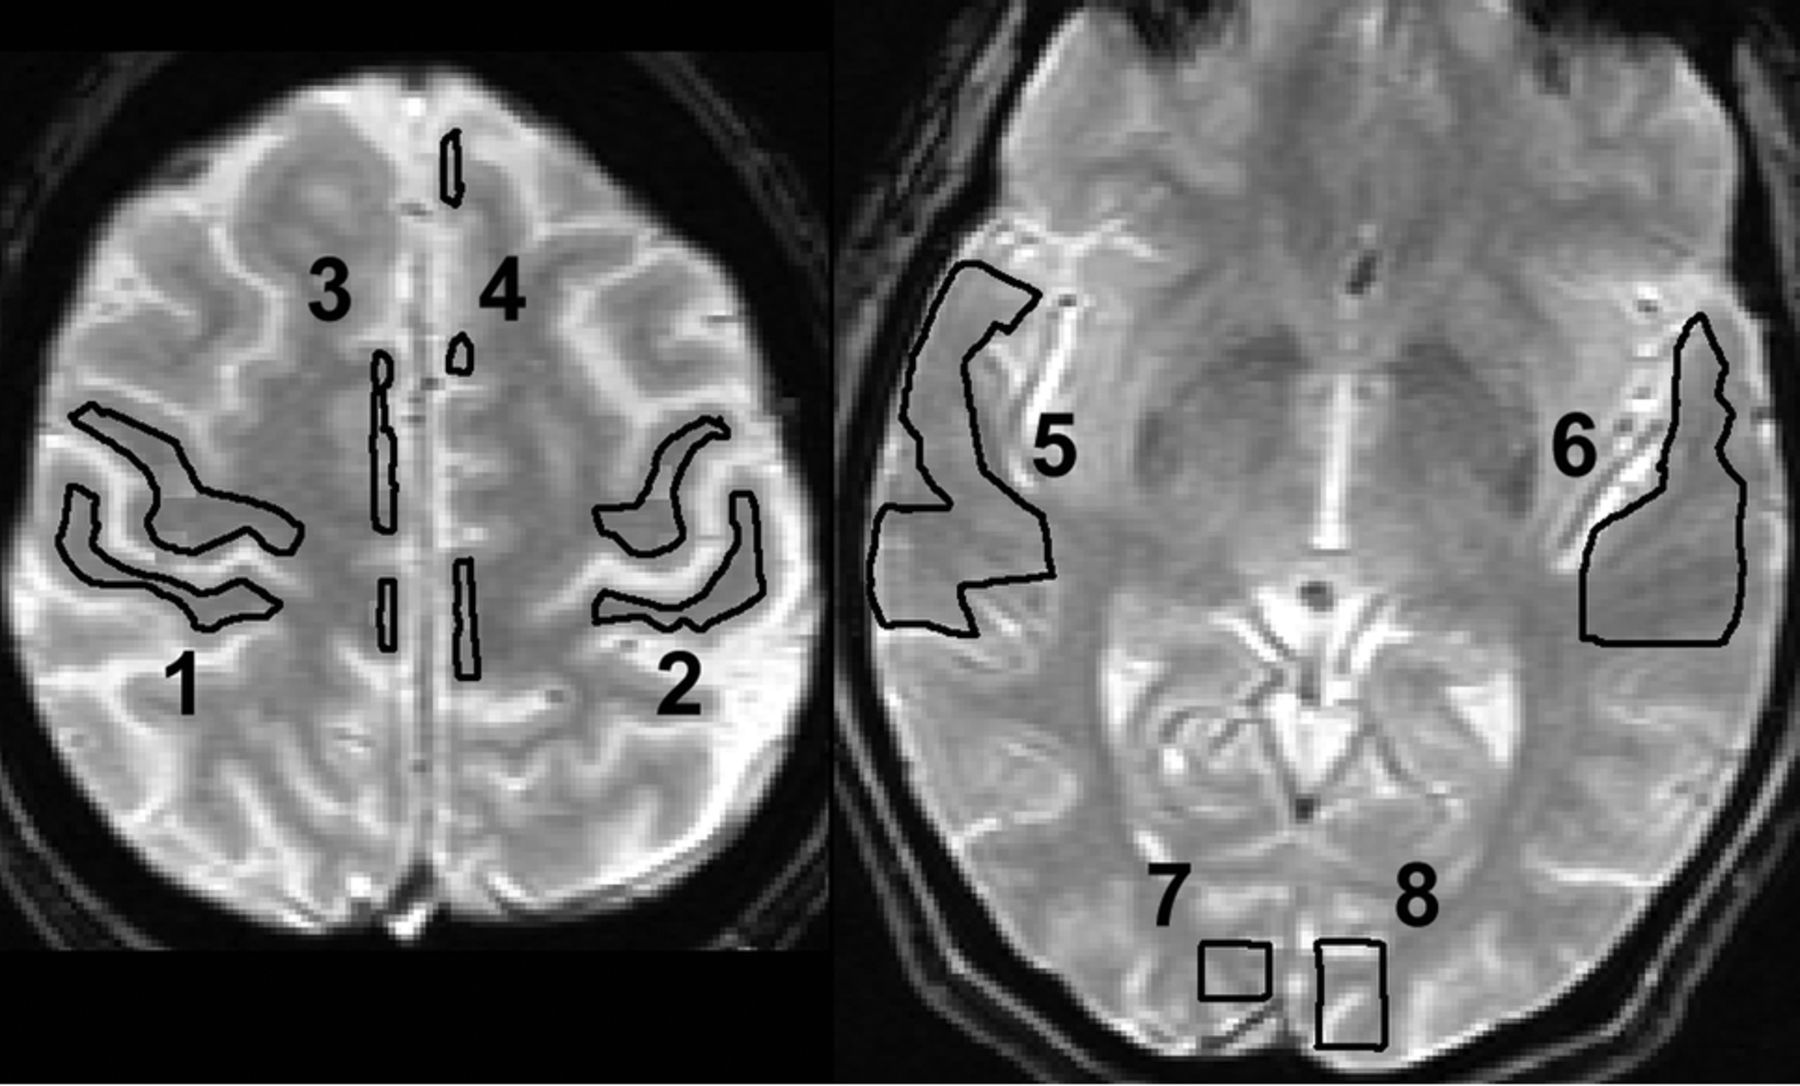

Time course data were analyzed by a voxelwise fitting of a γ variate function to the contrast agent concentration–time-series using a multivariate nonlinear least-squares fitting algorithm as described in detail elsewhere.8,9 The fitted points were limited to the initial baseline, leading edge, and the initial portion of the trailing edge after the peak (<4 points) to avoid contamination from contrast recirculation. Although other methods may be used,10 this γ variate method avoids bias from the choice of the arterial input function in the setting of CVD.11,12 The MTT was defined as the first moment of the γ variate function fitted to the contrast agent concentration–time-series. The relative CBV was the integral of the γ variate function. Only the results for MTT are shown because the CBV replicated the same responses. The perfusion parameters (MTT, CBV) were obtained pre- and postvasodilation from ROIs placed in the expected gray matter of fMRI activation in the vascular territory of each cerebral artery using the aligned high-resolution anatomic image (Fig 1). Each ROI contained at least 15 voxels and had a minimum contrast-to-noise ratio of 5. The means and SDs of each perfusion parameter were compared across vascular territories both before and after vasodilation. For SVDd and SVDp, the mean perfusion parameters were compared between cerebral hemispheres (4 left-right comparisons). For patients with MMD, the anterior vascular territories (ACA, sMCA, inferior division of the MCA) were compared with the ipsilateral PCA territories (6 anteroposterior comparisons). Depending on the complexity and distribution of disease in patients with MVD, either left-right or anterior-posterior comparisons were used between vascular territories with and without proximal disease.

ROIs were drawn manually on anatomic T2-weighted images coregistered with the perfusion images in each of the vascular territories in which regional BOLD activation is expected anatomically (1 and 2: right and left primary sensorimotor areas; 3 and 4: right and left supplementary motor areas; 5 and 6: right and left primary auditory areas; and 7 and 8: right and left primary visual areas). Voxels were included in the ROI if they were >50% within the boundary.

Representative patterns of BOLD activation for the HR assessment paradigm and for normal perfusion MTT pre- and postvasodilation in the primary sensorimotor cortex for subjects without CVD are shown in Fig 3. The BOLD pattern shows activation in the supplementary motor and primary sensorimotor areas. The primary auditory and primary visual and visual association areas (not shown) are equally robust. The perfusion maps without vascular disease are reproducible pre- and postvasodilation and symmetric in both left-right and anteroposterior comparisons.

A, Normal sensorimotor activation pattern for BOLD fMRI with the HR assessment paradigm. Areas of activation are the following: 1) right primary sensorimotor cortex (right sMCA), 2) left primary sensorimotor cortex (left sMCA), and 3) left and right supplementary motor area (left and right ACA, respectively). The color scale reflects the continuous t value (threshold t = 3 red, t > 3 yellow) of the activation-detection statistics. B, Normal quantitative perfusion map of MTT at the same level as A remains symmetric before and after vasodilation. The color scale is in seconds.